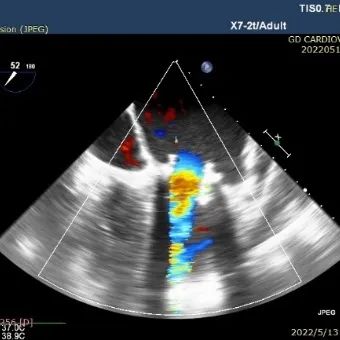

经食道心脏彩超检查显示,介入瓣形态位置良好,无明显瓣周漏,舒张期前向血流通畅。移除加硬导丝,并收紧心尖荷包缝线打结固定。

球囊后扩;舒张期J-Valve瓣膜前向血流通畅;收缩期未见明显瓣周漏